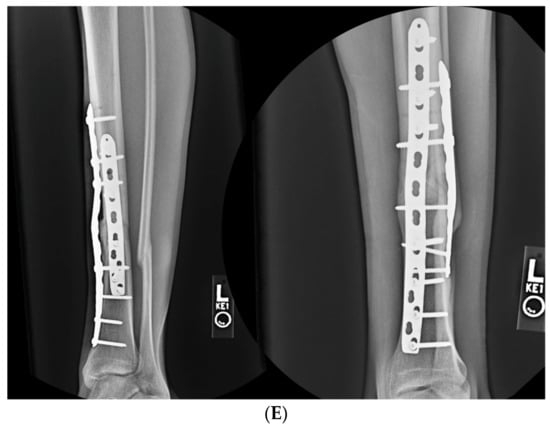

3.2. Case 2-Single-Plane Correction with Plate Fixation: Tibia

A young adult college baseball player presented with symptoms of lateral proximal knee pain and a feeling of knee instability 8 months after sustaining a closed fracture of the tibia, initially treated closed with casting (Figure 7A). The patient underwent a workup including full-length films, knee MRI, and local anesthetic test injection of the proximal tibiofibular joint (relieving knee pain). The CORA analysis revealed a recurvatum deformity of 10 degrees and varus deformity of 3 degrees, with translation in the coronal plane. Full-length alignment film of the pelvis and lower extremity confirmed coronal translation with mild varus angulation (Figure 7B). The true plane of deformity was calculated approximately 75 degrees from the coronal plane (15 degrees off-sagittal) with a magnitude of between 10 and 11 degrees.

(A) A young adult college baseball player sustained a closed tibia fracture with intact fibula, treated closed. The patient developed a recurvatum deformity with pain at the proximal and distal tibiofibular joints. (B) The patient demonstrated mechanical axis lateralization due to coronal plane translation with slight varus. The plane of deformity was calculated as 73 degrees off of the coronal plane. (C) The patient underwent focal dome osteotomy at the CORA (yellow circle) in the plane of maximum deformity. (D) Dual plate compression was used. Angulation and translation were simultaneously corrected. (E) Final follow-up 9 months: anteroposterior, lateral, and oblique films show the osteotomy healed. Tibiofibular joint pain resolved after osteotomy. Patient returned to college-level baseball.

A focal dome was chosen to correct the varus recurvatum and translation. The surgical approach was an anterior approach over the anterior compartment, elevating the tibialis anterior from the lateral tibia to allow safe access to the plane of the deformity. The fibula was osteotomized near the level of the tibia through a separate lateral approach. The plane of maximum deformity was assessed intraoperatively and confirmed the preoperative calculations. The ‘no deformity’ view on fluoroscopy was located, with the maximum plane orthogonal to this. It is in this plane that the drill bit at the CORA is directed, and this is especially important if correcting a translation. The arc of the osteotomy was drawn using a parallel drill guide with one bit centered at the CORA (Figure 7C).

The angulation and translation were simultaneously corrected. Dual medial–lateral plates were used to counteract the lateral gap forming with medial plate compression. Hence, balanced compression from the medial and lateral plates restored the alignment and provided absolute stability (Figure 7D). The patient had immediate relief of knee pain after correction. The soft tissue and osteotomy healed without incident (Figure 7E).